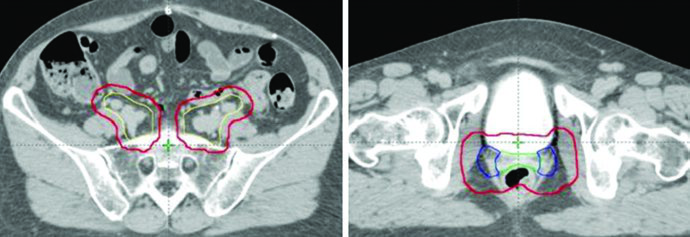

In endometrial cancer patients, CTV3 is modified to include the presacral region when cervical stromal invasion is present. When pathologic involvement of para-aortic or high common iliac nodes is confirmed, extended pelvic-para-aortic fields are used, with the upper border of the CTV extending to the T12-L1 or L1-L2 interspace, or the renal vasculature.

For cases with distal one-third vaginal involvement, inguinal nodes should be contoured continuously from the external iliac nodes to 2 cm caudal to the saphenous-femoral junction.

A boost of 5-15 Gy may be added for gross nodal disease or parametrial involvement, delivered either sequentially or as a simultaneous integrated boost (SIB). The textbook illustrates a patient with FIGO stage IB endometrioid adenocarcinoma, post robotic-assisted laparoscopic hysterectomy, who had an enlarged para-aortic lymph node found at CT simulation. She was treated with extended field IMRT using an ITV technique. The superior border of CTV3 was modified to include the renal hilum, the GTV of gross nodal disease was contoured, and it received a planned SIB boost of 5940 cGy with 4760 cGy in 28 fractions to the remaining nodes.